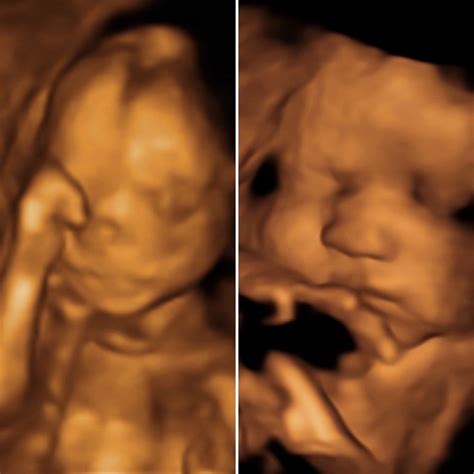

Understanding the Ultrasound Images

The 16 week ultrasound provides detailed images of the baby’s anatomy. Healthcare providers will look for specific features to ensure everything is developing normally. Some of the key areas of focus include:

• Head and Brain: The shape and size of the head, as well as the development of the brain structures.

• Limbs: The length and structure of the arms and legs, including the hands and feet.